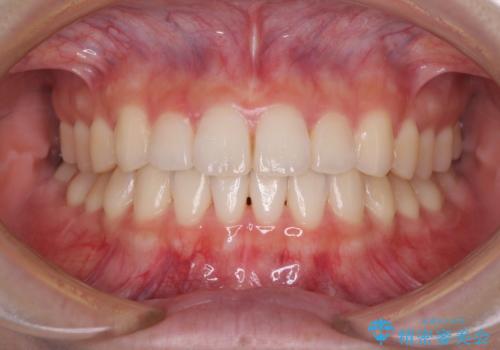

本来、あまりにも不自然な歯となるため、フルジルコニアクラウンを前歯に使用することは、咬合力が強すぎる場合を除き、ほとんどありません。

それでも、色調、形態ともに不自然なくらい真っ白な歯をご希望でしたので、患者様には大変満足していただきました。